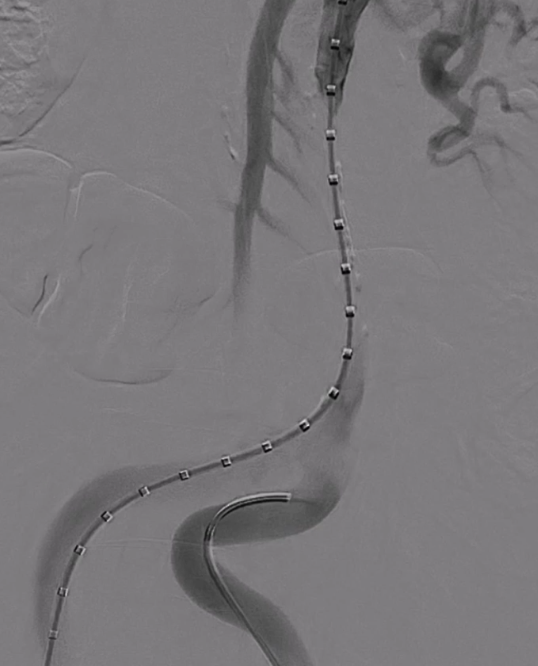

从右侧股动脉入路,使用超滑导丝进入真腔,置入金标猪尾导管造影,再次造影明确夹层真腔位置、形态,可见腹主动脉及降主动脉真腔处多处严重狭窄受压,假腔呈瘤样扩张并累及左侧锁骨下动脉。

通过左侧股动脉入路置入猪尾导管,并在超硬导丝引导下置换24F大鞘,缓慢送入防缠绕导管至主动脉弓部。

3. 关键分支处理环节,分支导丝超选与抓捕建立分支导丝通路

使用4F 导管和抓捕系统,分别超选弓上三分支(无名动脉、左颈总、左锁骨下动脉)

14系统导丝经防缠绕导管引出至右侧股动脉输送鞘外,建立分支导丝通路。

无旋转状态下撤出防缠绕导管。

根据详细测量数据,选用型号为 F46-40-45-191-16-14-14 FixTa一体化三分支主动脉覆膜支架支架系统。

沿超硬导丝将主体缓慢送入主动脉弓部,透视下确保导丝无缠绕。

调整支架位置,确保主体分支支架对应无名动脉、左颈总动脉及左锁骨下动脉开口位置满意。